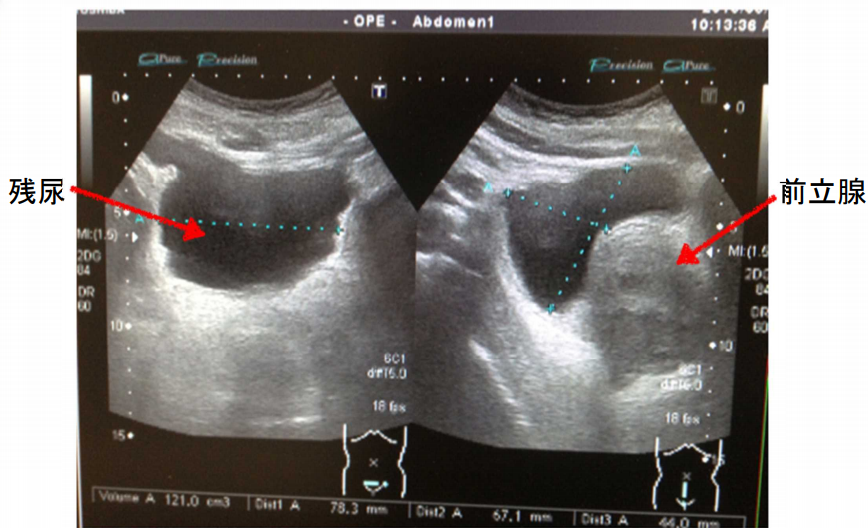

残尿

残尿とは、排尿後も膀胱内に尿が残る状態をいいます。

尿道が圧迫されると、尿を全部出せず 残尿が増えてきます。

尿を溜める膀胱のスペースが減るため、1回の排尿量は少なく、何回もトイレに行くようになります。30代後半以降の男性は注意。